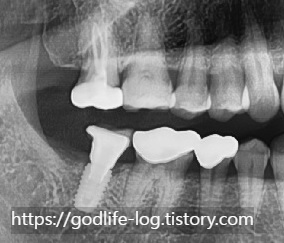

이렇게 치아는 서로 맞닿는 치아가 없으면 위로 솟거나 아래로 내려옵니다. 하지만 이렇게 위아래치아만 영향을 받는 것이 아니라 양 옆 치아도 치아가 없는 쪽으로 기울어지게 됩니다.

이렇게 치아가 기울어진 상태로 임플란트 보철물을 완성할 경우 위치나 방향 때문에 보철물 모양이 조금 달라질 수 있고 치아와 치아 사이 공간이 넓어져서 음식물이 잘 낄 수 있습니다. 너무 많이 기울어져있는 경우는 위에서 말씀드린 바와 같이 치아를 신경치료하고 크라운 치료를 같이 해야 할 수도 있습니다.